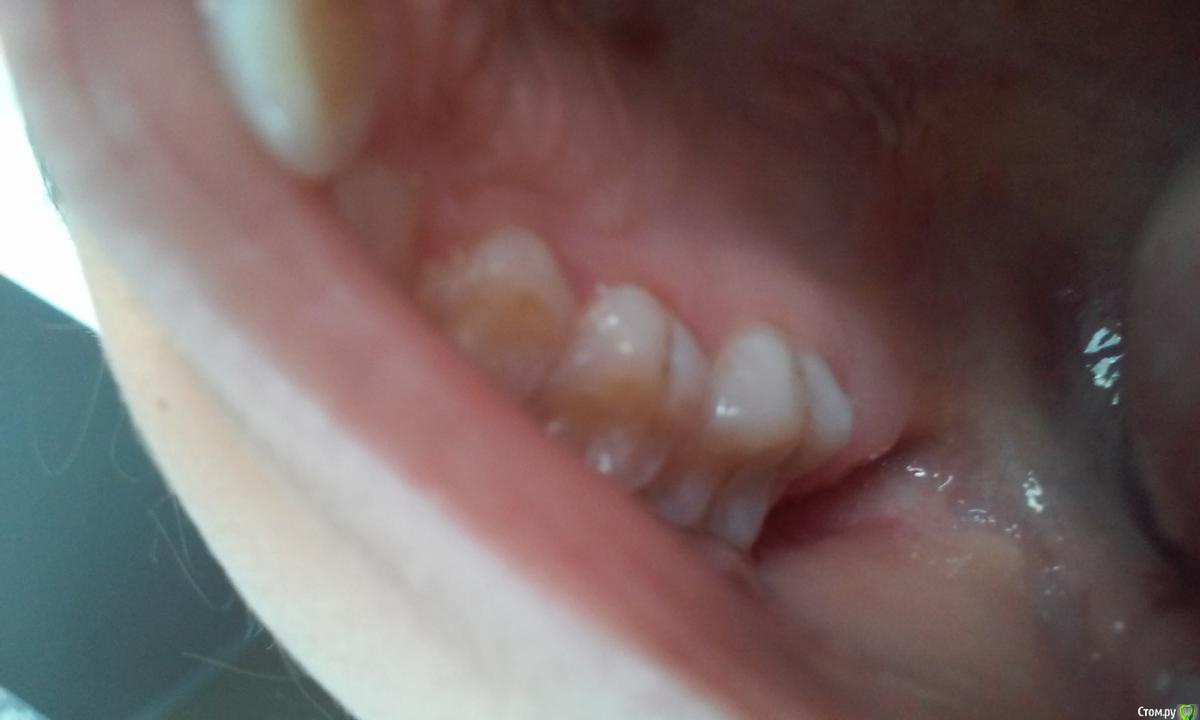

Маргарита1234 Опубликовано 3 октября, 2015 Поделиться Опубликовано 3 октября, 2015 Здравствуйте, уважаемые стоматологи! Очень прошу о помощи. У дочери 9 лет на постоянных зубах на верху и внизу черные единичные точки, а также бороздочки сбоку зуба, меня это тревожит, 1 раз в 6 мес. делаем в поликлинике кальцинирование, затем фтором покрываем, всегда тщательно следили за зубами, врач сказала, что это не кариес и удалять не нужно,т.к. могут вновь появиться. Проверили у лора, обнаружили золотистый стафиокок, лечим, проверяемся у гастроэнтеролога, но от чего такие бороздочки на зубах???? Что делать, какие анализы сдавать. И ещё, наносим сами гель Рокс. Ссылка на комментарий

red_butler Опубликовано 3 октября, 2015 Поделиться Опубликовано 3 октября, 2015 Похоже на кариес 1 Ссылка на комментарий

Джима Опубликовано 4 октября, 2015 Поделиться Опубликовано 4 октября, 2015 (изменено) там герметик что ли? герметизировали фиссуры? в нижнем зубике мне похоже как по краю герметика либо пигментация фиссуры, либо уже кариес. в верхнем - скорее всего небольшой кариес. но по фото однозначно не скажешь Изменено 4 октября, 2015 пользователем Джима Ссылка на комментарий